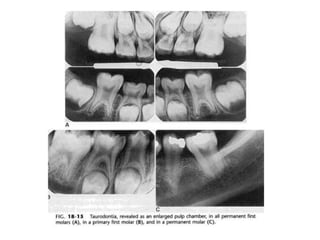

9. Taurodontism

Body dari gigi yang taurodont tampak

memanjang dan akarnya pendek.